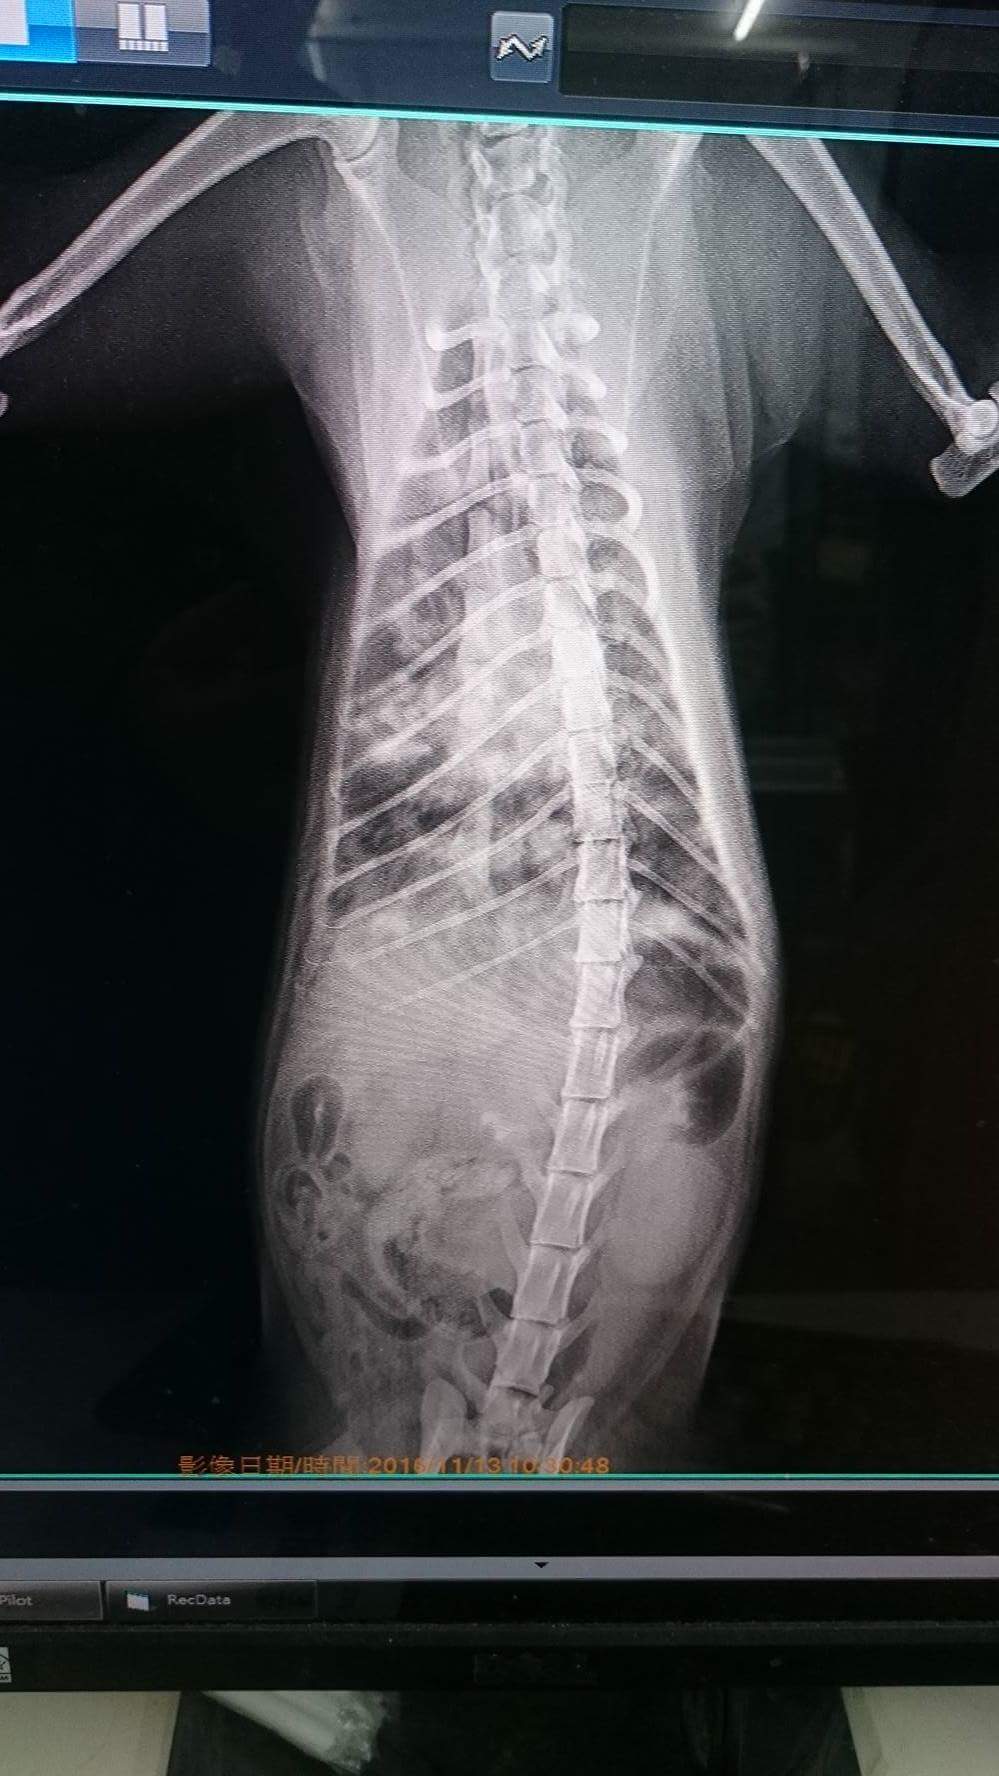

11/13一早就趕緊送往協會所配合的醫院《綠光動物醫院》看診過程抱她出外出籠 呼吸急促很喘 所以先做了血檢拍X光片並給予氧氣。

血檢報告 白血球偏低淋巴球偏低 X光片顯示肺部極為不尋常 醫生說是肺炎 先住院氧氣治療 因已有輕微脫水 所以同時給予皮下點滴補充水分穩定電解質 先將呼吸急促情況穩住 若2~3天情況不見改善 須檢驗何種病毒造成感染 才能做細菌培養醫療 給予治療藥物。

X光片(2張)1000×3=$3000(住院期間預估拍X光的次數)